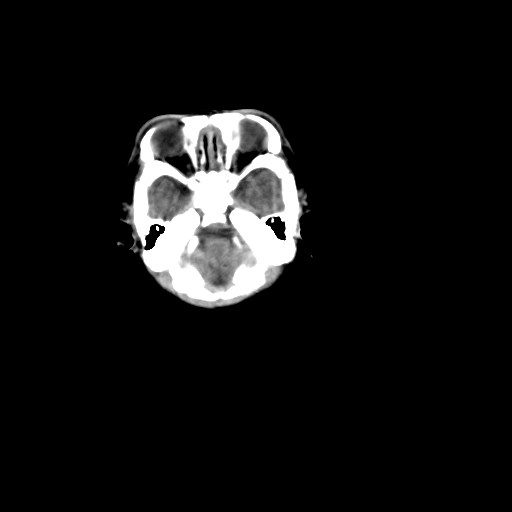

男,12天,自然分娩,其母发现右顶部头皮包块逐渐增大。

右顶部头颅血肿(骨膜下血肿)

骨膜下血肿

右顶部头皮血肿,可能是产道挤压所致。以后会慢慢恢复。

鉴别:骨膜下血肿,一般为产伤,应用产钳之类的吧

右顶部头颅血肿(骨膜下血肿).

右顶部骨膜下血肿。